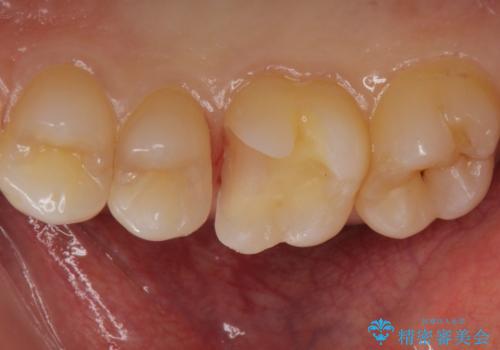

白くて適合の良い詰め物が入りました。

e-maxインレーは保険のインレーに比べて虫歯の再発のリスクが低くなります。